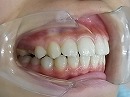

今回はt4kによって下顎後退症を改善している症例を御報告したいと思います。

下顎後退症 といっても多分聞きなれない病名だと思います。

一般的には出っ歯と言われていますが、この状態には2つのタイプがあります。

1、上顎の前歯の部分が成長しすぎているタイプ

2、下顎全体が後退しているタイプ

割合としては、下顎が後退しているタイプが殆どです。

トレーナーを使用して、後退している下顎を本来の位置に戻すために使用しています。

トレーナー使用中 使用開始時の状態

使用して5カ月後